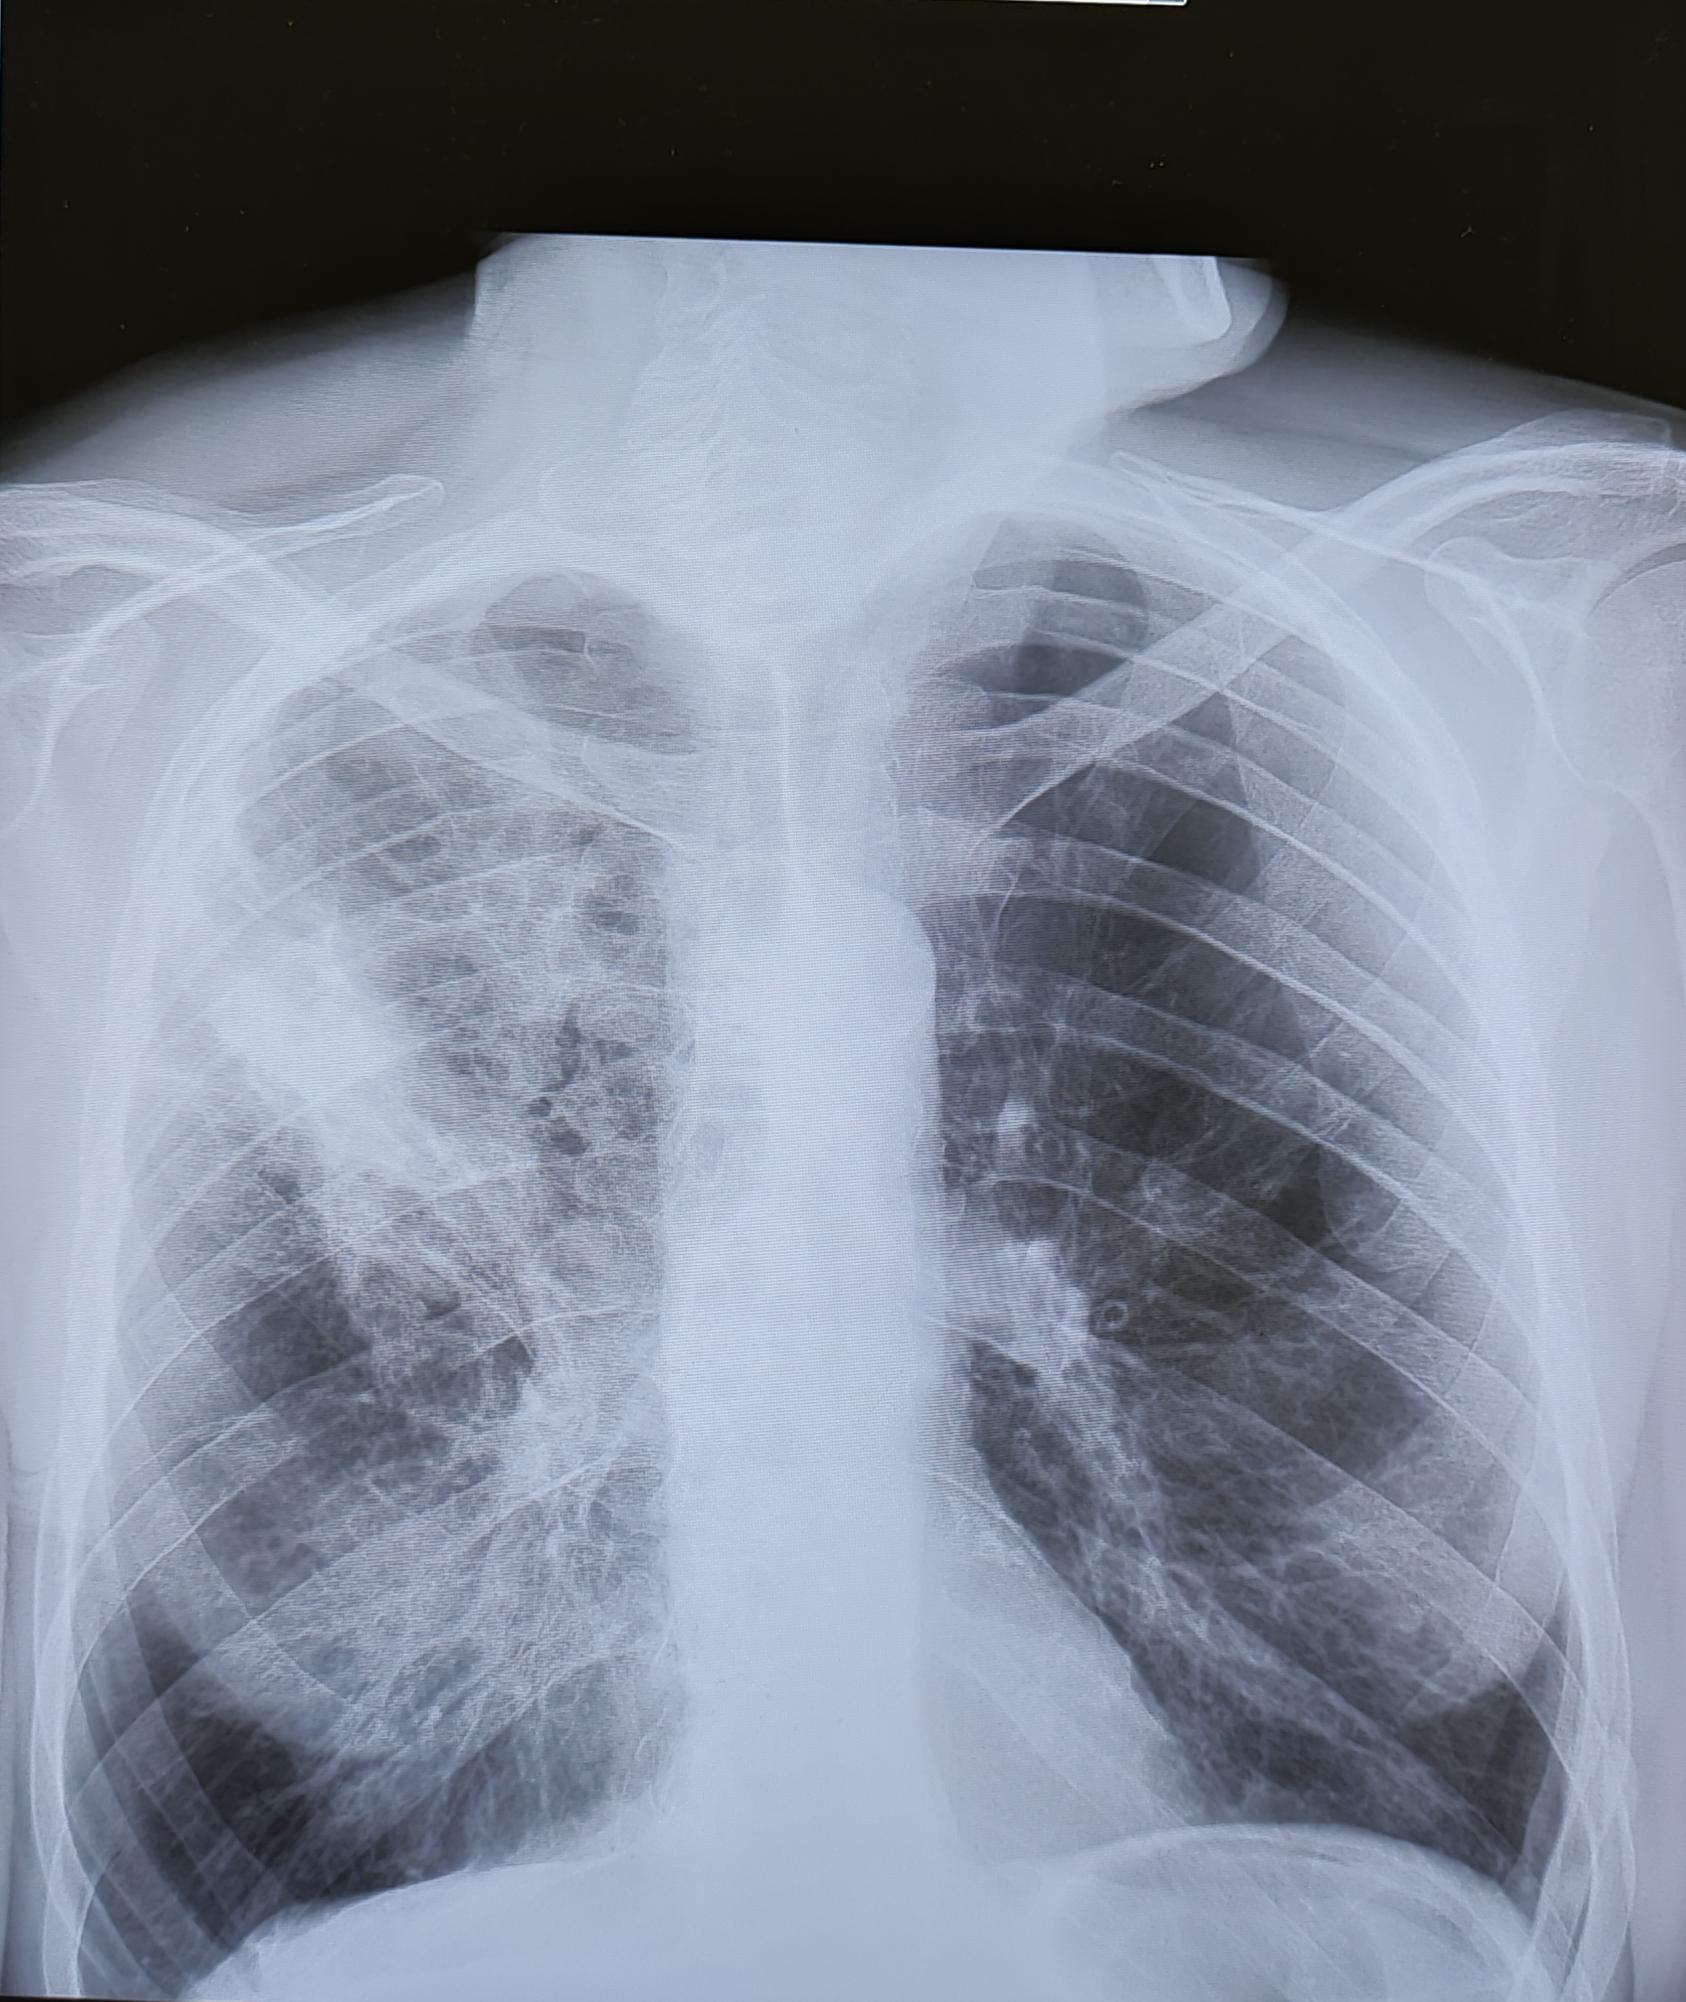

Внебольничная пневмония-рентген

На Р-граммах ОГК в 3х проекциях: На фоне сниженной пневматизации, визуализируются инфильтративные изменения легочной ткани в S2, S3 правого легкого. Легочный рисунок усилен за счет сосудистого компонента. Корень слева-не увеличен, справа-увеличен. Диафрагма не изменена, контуры ее ровные, четкие. Тень сердца обычного расположения не расширена в поперечном размере. Дуга аорты склерозирована. Дегенеративно-дистрофические изменения грудного отдела позвоночника.

Заключение: Правосторонняя бисегментарная S2, S3 пневмония.